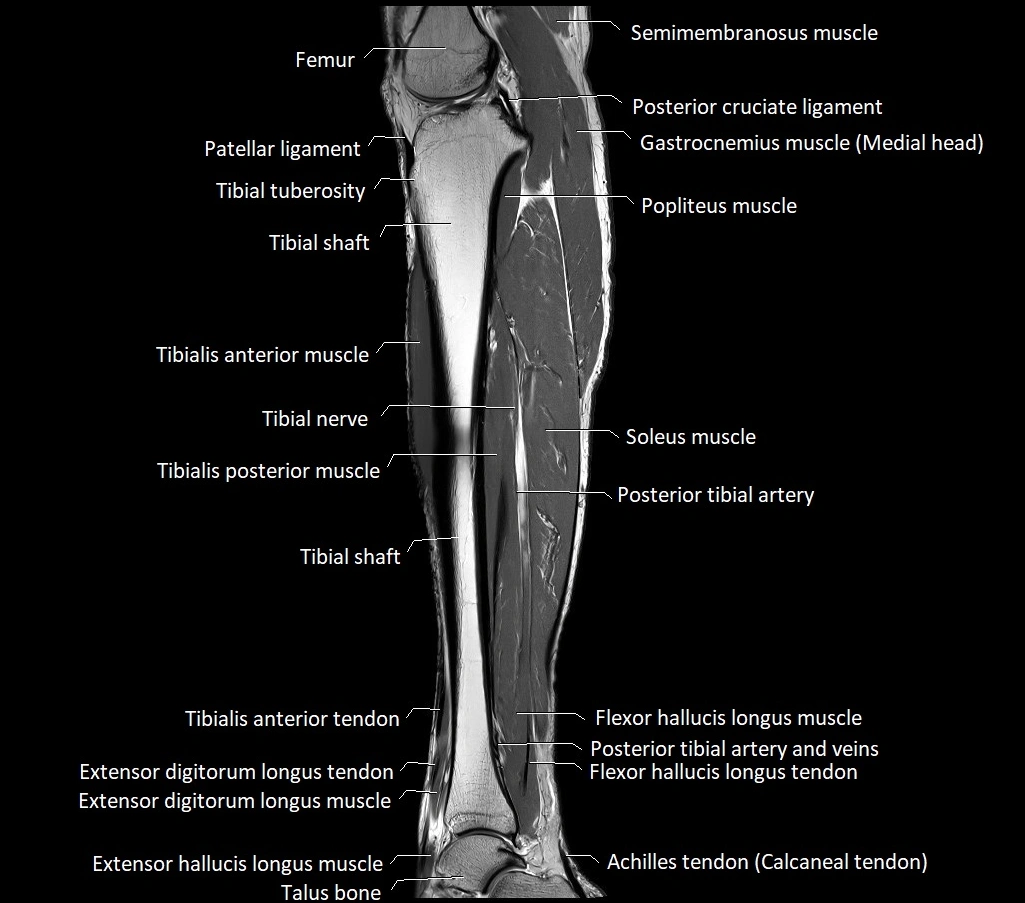

MRI image